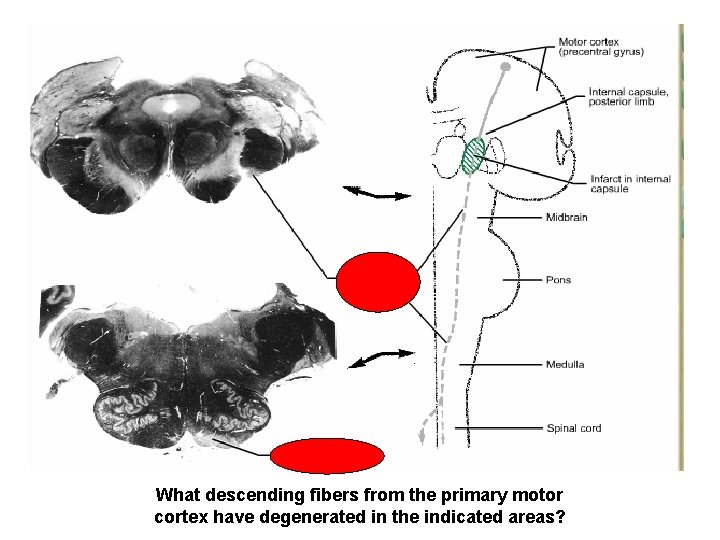

What descending fibers from the primary motor cortex have degenerated in the indicated areas?